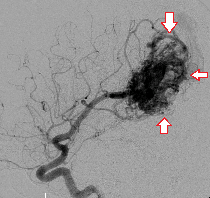

(下図)けいれんで発症した大型の脳動静脈奇形を、液体塞栓物質Onyxを用いて塞栓しました。ほぼ完全な閉塞が得られています。

脳動静脈奇形

塞栓術後